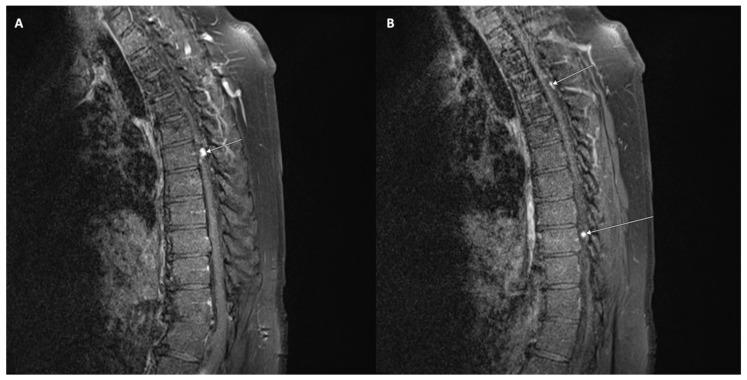

The present review aimed to establish an understanding of the pathophysiology of leptomeningeal disease as it relates to late-stage development among different cancer types. For our purposes, the focused metastatic malignancies include breast cancer, lung cancer, melanoma, primary central nervous system tumors, and hematologic cancers (lymphoma, leukemia, and multiple myeloma). Of note, our discussion was limited to cancer-specific leptomeningeal metastases secondary to the aforementioned primary cancers. LMD mechanisms secondary to non-cancerous pathologies, such as infection or inflammation of the leptomeningeal layer, were excluded from our scope of review. Furthermore, we intended to characterize general leptomeningeal disease, including the specific anatomical infiltration process/area, CSF dissemination, manifesting clinical symptoms in patients afflicted with the disease, detection mechanisms, imaging modalities, and treatment therapies (both preclinical and clinical). Of these parameters, leptomeningeal disease across different primary cancers shares several features. Pathophysiology regarding the development of CNS involvement within the mentioned cancer subtypes is similar in nature and progression of disease. Consequently, detection of leptomeningeal disease, regardless of cancer type, employs several of the same techniques. Cerebrospinal fluid analysis in combination with varied imaging (CT, MRI, and PET-CT) has been noted in the current literature as the gold standard in the diagnosis of leptomeningeal metastasis. Treatment options for the disease are both varied and currently in development, given the rarity of these cases. Our review details the differences in leptomeningeal disease as they pertain through the lens of several different cancer subtypes in an effort to highlight the current state of targeted therapy, the potential shortcomings in treatment, and the direction of preclinical and clinical treatments in the future. As there is a lack of comprehensive reviews that seek to characterize leptomeningeal metastasis from various solid and hematologic cancers altogether, the authors intended to highlight not only the overlapping mechanisms but also the distinct patterning of disease detection and progression as a means to uniquely treat each metastasis type. The scarcity of LMD cases poses a barrier to more robust evaluations of this pathology. However, as treatments for primary cancers have improved over time, so has the incidence of LMD. The increase in diagnosed cases only represents a small fraction of LMD-afflicted patients. More often than not, LMD is determined upon autopsy. The motivation behind this review stems from the increased capacity to study LMD in spite of scarcity or poor patient prognosis. In vitro analysis of leptomeningeal cancer cells has allowed researchers to approach this disease at the level of cancer subtypes and markers. We ultimately hope to facilitate the clinical translation of LMD research through our discourse.

本综述旨在了解脑膜疾病的病理生理学,因为它与不同癌症类型的晚期发展有关。为此,我们重点关注转移性恶性肿瘤,包括乳腺癌、肺癌、黑色素瘤、原发性中枢神经系统肿瘤和血液系统癌症(淋巴瘤、白血病和多发性骨髓瘤)。值得注意的是,我们的讨论仅限于上述原发性癌症引起的癌症特异性脑膜转移。我们的综述范围不包括非癌症病理引起的脑膜疾病机制,例如脑膜层的感染或炎症。此外,我们旨在描述脑膜疾病的一般特征,包括特定的解剖学浸润过程/区域、CSF 传播、患有该疾病的患者的临床表现、检测机制、成像方式和治疗方法(临床前和临床)。在这些参数中,不同原发性癌症的脑膜疾病具有几个共同特征。所提到的癌症亚型中 CNS 受累的发展的病理生理学在性质和疾病进展上相似。因此,无论癌症类型如何,脑膜疾病的检测都采用了几种相同的技术。脑脊液分析结合各种成像(CT、MRI 和 PET-CT)在当前文献中被认为是脑膜转移诊断的金标准。鉴于这些病例很少见,因此脑膜疾病的治疗选择多种多样,且仍在不断发展。我们的综述详细说明了几种不同癌症亚型的脑膜疾病之间的差异,旨在突出靶向治疗的现状、治疗的潜在缺陷以及未来临床前和临床治疗的方向。由于缺乏全面的综述,试图将脑膜转移的特征从各种实体瘤和血液瘤癌症中概括出来,作者不仅旨在强调重叠的机制,还旨在强调疾病检测和进展的独特模式,以便对每种转移类型进行独特的治疗。脑膜疾病病例的稀缺性对这种病理学的更深入评估构成了障碍。然而,随着原发性癌症治疗的改善,脑膜疾病的发病率也有所提高。诊断出的病例增加仅代表受脑膜疾病影响的患者的一小部分。通常情况下,脑膜疾病是在尸检时确定的。进行此综述的动机源于尽管病例稀少或患者预后不佳,但仍有能力研究脑膜疾病。脑膜癌细胞的体外分析使研究人员能够在癌症亚型和标志物的层面上研究这种疾病。我们最终希望通过我们的论述促进脑膜疾病研究的临床转化。